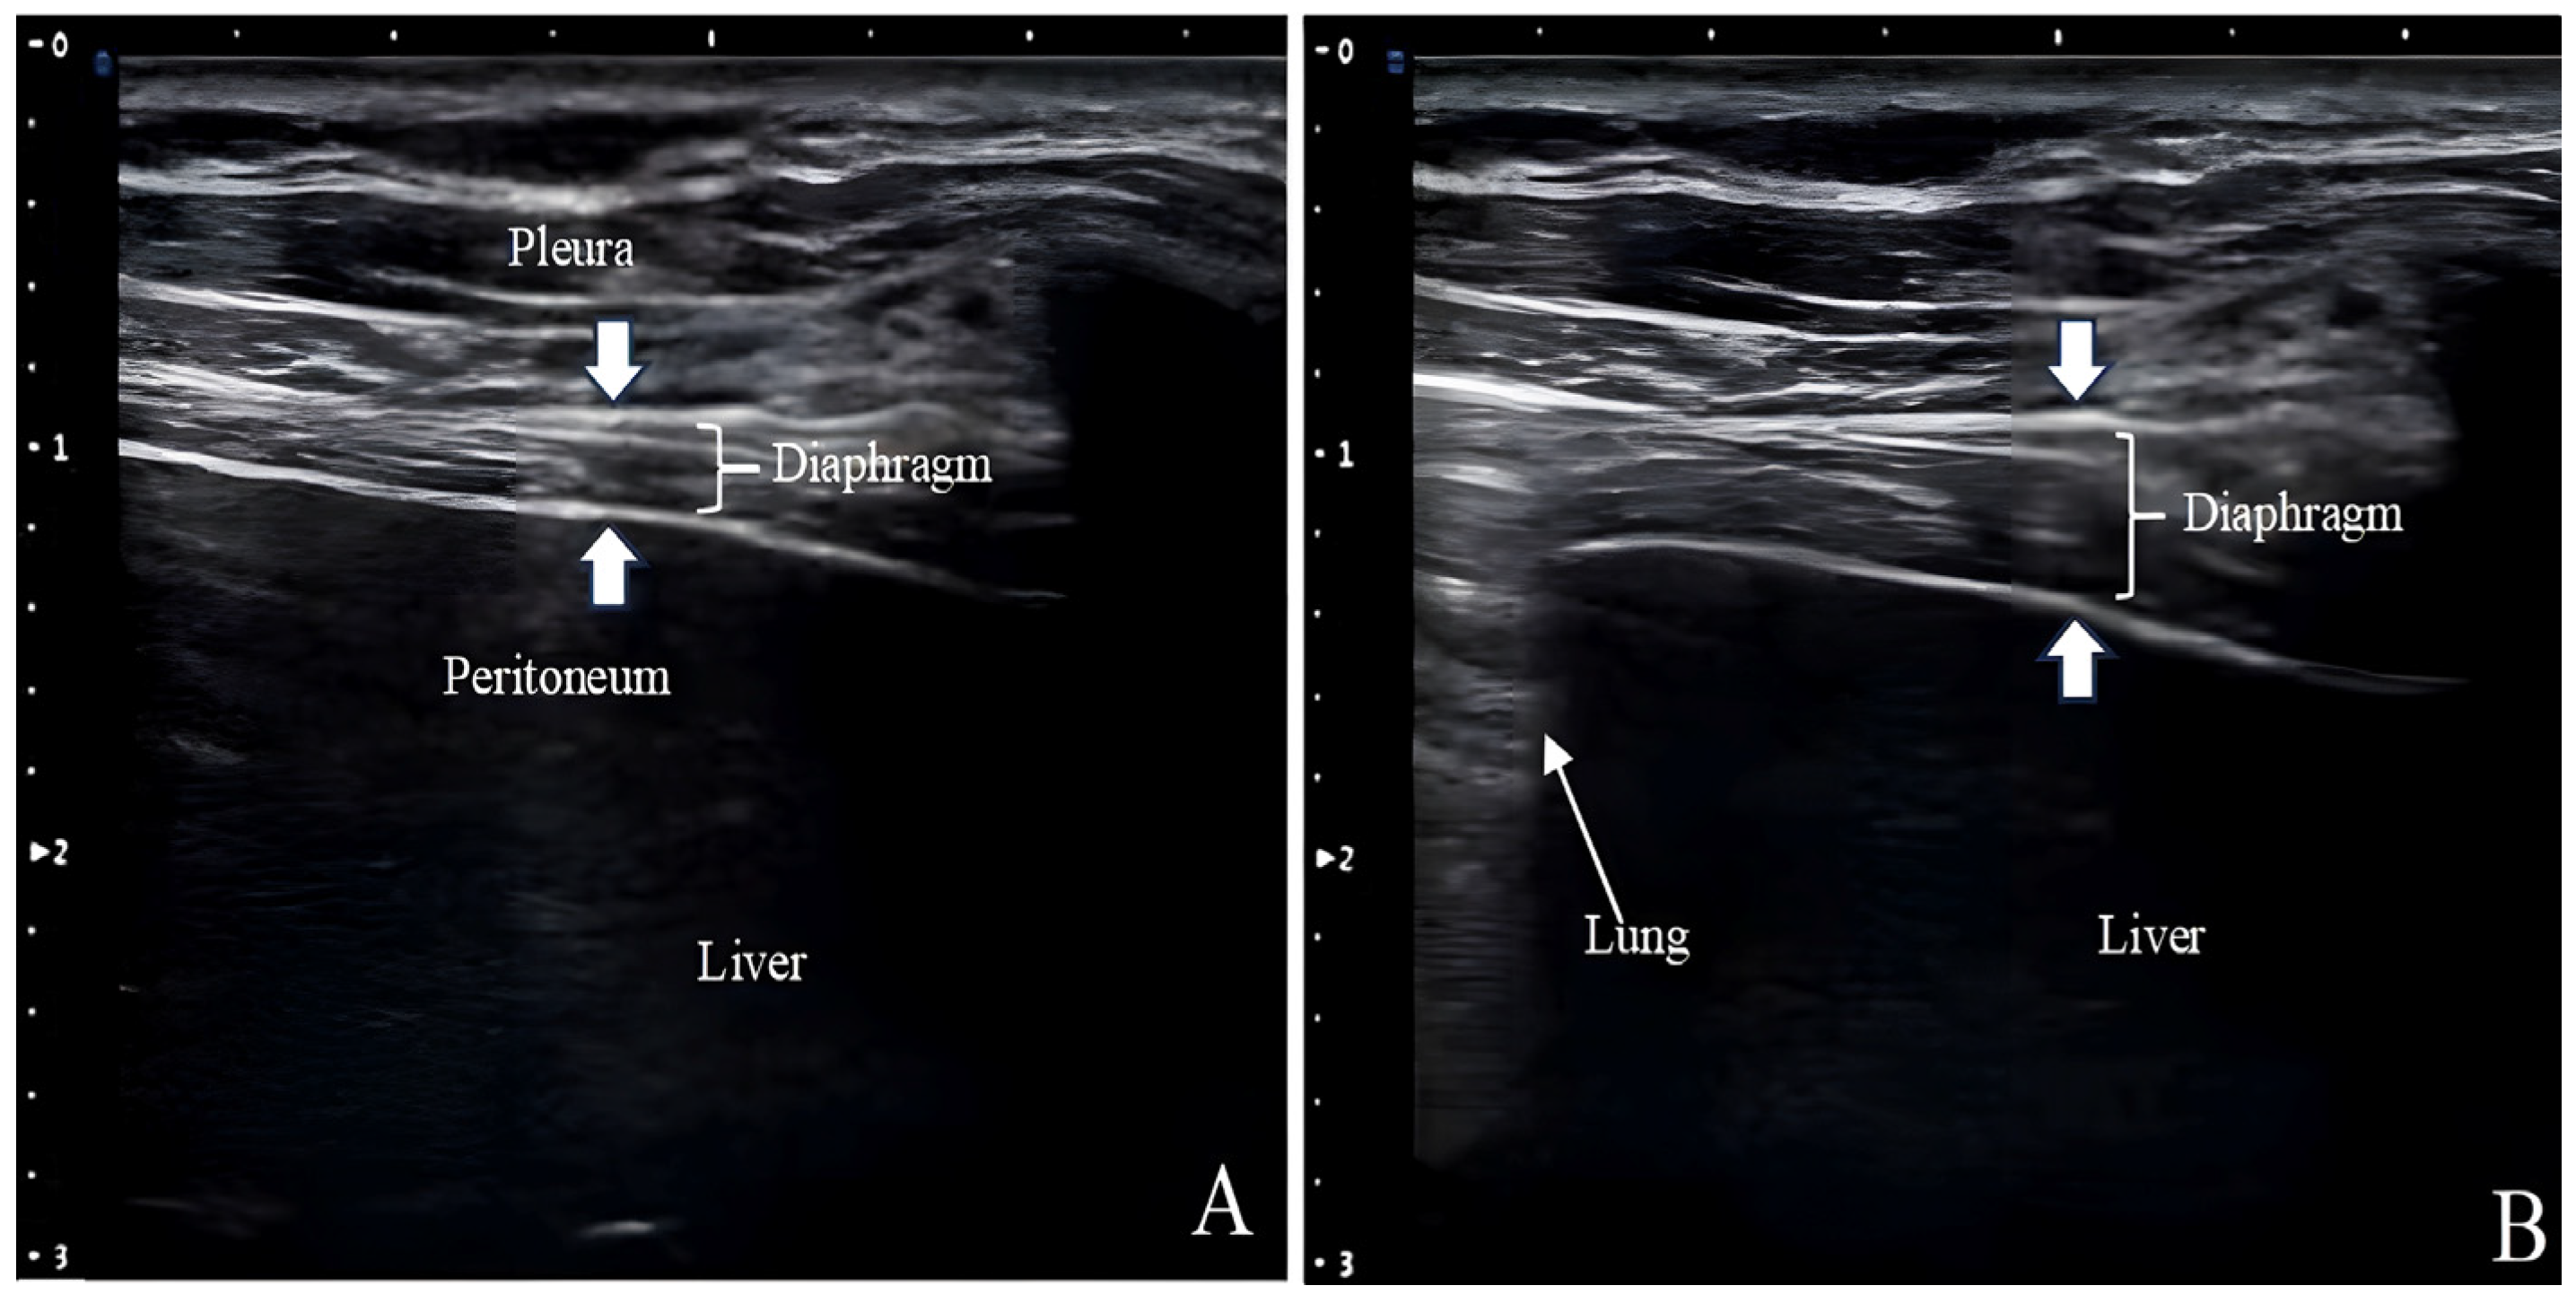

4.5.2. Tdi

Ultrasound measurements of Tdi have been used to assess diaphragm atrophy in patients with neuromuscular disorders and those requiring MV (Figure 3) [53,54]. The Tdi during inhalation is comparable to the cardiac ejection fraction and is a reliable respiratory effort indicator [55]. The lower Tdi limit for normal adults is 0.80–1.60 mm, and posture, lung volume, and selected intercostal space can affect the measurements [36]. Given that Tdi is measured in millimeters off the ultrasound screen with a cursor of a certain thickness and from a tracing that may not be perfectly outlined, it is susceptible to the “small number effect”.

Figure 3. Measurement of diaphragmatic thickness through B-Mode ultrasonography. The distance between the pleura and peritoneum represents diaphragmatic thickness. The images show a change in normal diaphragm thickness between end-exhalation (A) and end-inspiration (B). The lung is visualized at end-inspiration.